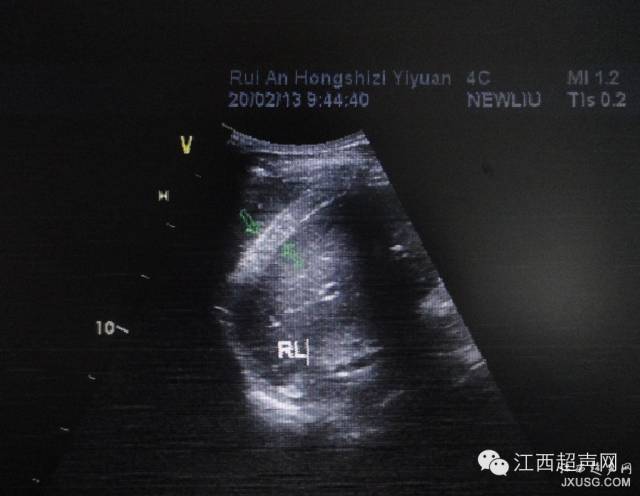

51.检查妇科、膀胱,膀胱需要适当充盈,强调“适当”。看看这个膀胱,是不是很像后壁的病变?

彩超伪像是什么60个超声诊断中容易误诊的正常结构_https://www.jmylbn.com_新闻资讯_第10张